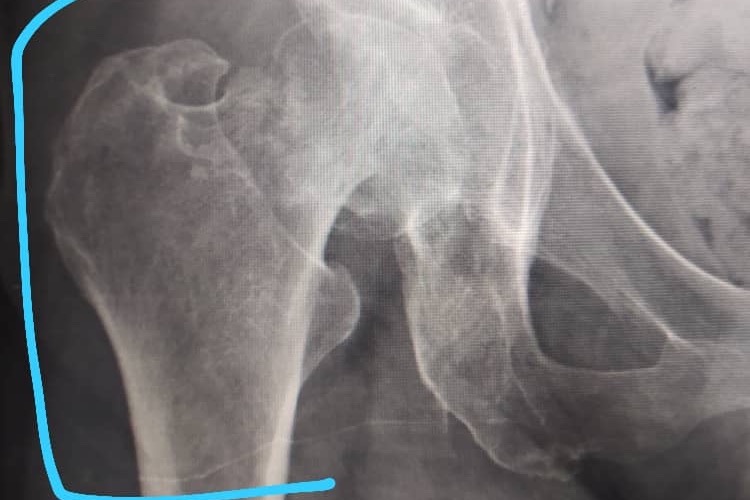

El día 02 de marzo del 2021, mi abuela se          encontraba en su casa, estaba en el baño como un día normal y al salir de este, intentó agarrarse de la puerta del baño para evitar caerse         falló en el intento y se golpeó en la pierna derecha, le dolía mucho y no podía caminar, al            llevarla hoy 03/03 a realizarse una placa nos   enteramos de que efectivamente tiene una      FRACTURA en la cabeza del fémur